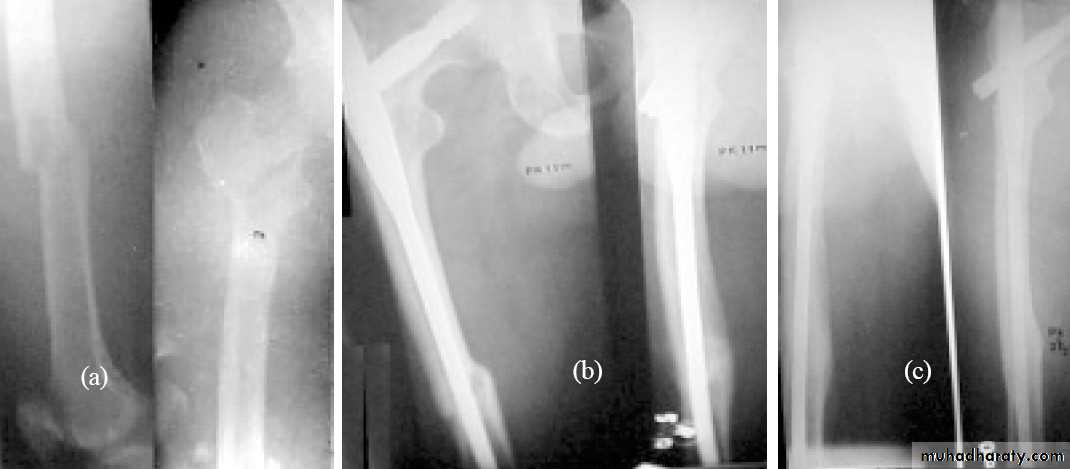

Inter-trochanteric fractures (extracapsular fracture)

.It is extra capsular fracture occurs in elderly..Unite quite easily and seldom cause a vascular necrosis.

Same previous principle almost always treated by early internal fixation.(to overcome) the possible complications associated with prolonged recumbency.

To get the patient up and walking as soon as possible.

1.Sliding nail

2.L-plate

3.External fixation

Gamma nail

Postoperative exercise is started as early as possible on the

( day after operation ).Patient is allowed up and partial weight bearing as soon as possible.